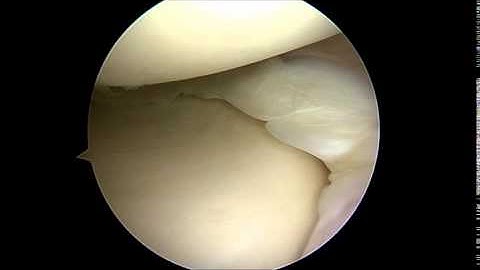

Meniscus Bucket Handle Tear